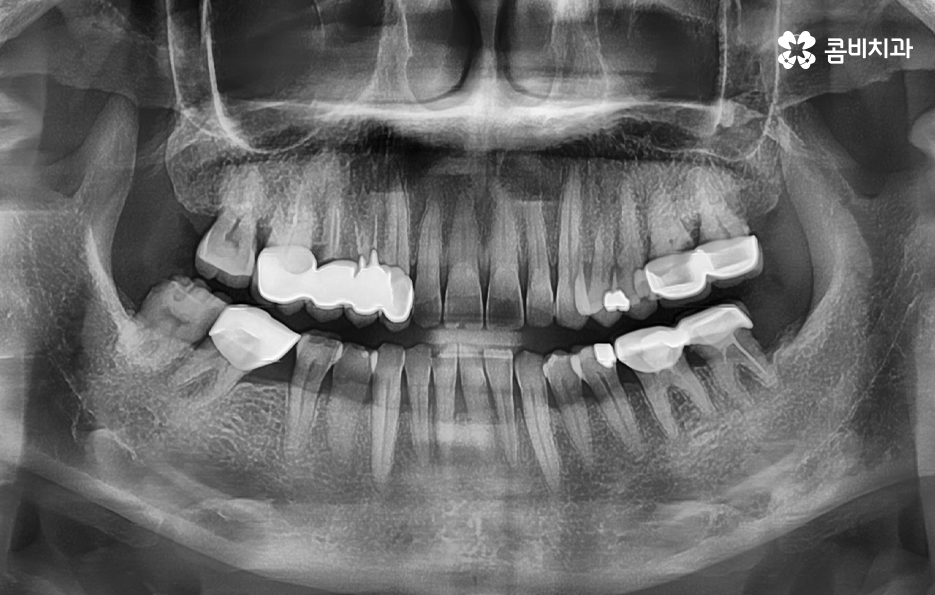

누구나 살다보면 치아에 충치부터 작은 깨짐 등으로 인해 요즘은 대부분 레진이지만 과거에는 아말감과 같은 치료를 해본 분들이 많을텐데 이러한 치과 보철치료를 받았던 분들이 시간이 지나면서 보철물 안으로 2차충치가 발생해서 고생하는 사례가 많이 있어요

과거에 충치로 인해 고생했던 분들 중에서 보통은 명동치과 치료 후에 수개월 혹은 수년간 치아에 별다른 불편함을 못느낀다면 치아가 건강하다고 믿는 분들이 많지만 보철물 속에 2차충치가 발생하는 사례처럼 우리 눈에 보이지 않는 곳에서는 치아 문제가 발생할 수 있다는 거예요

치아가 안아파도 명동치과 매년 주기적으로 검진하고 스케일링을 하시라고 권장하는 이유도 이러한 2차충치에 대한 우려 혹은 보철물의 교체 주기 및 수명을 체크하는 이유도 있겠고 사랑니 상태나 치아의 인접면에 발생하는 충치와 같이 평소 눈으로는 살펴보기 어려운 치아 문제를 치과에서 정확하게 파악하려는 목적이 크다고 할 수 있어요

많은 환자분들께서 이미 충치 치료를 했던 부위인데 왜 또 충치가 생길 수 있는지 의아해 하시는 분들도 계실 거예요. 충치 치료를 했던 부위를 살펴보면 보철 재료와 치아 사이에 경계면이 있다는 것을 알 수 있는데요.

충치 치료 후에는 보철물과 치아 사이의 경계선 부분에서 보철물의 접착제가 녹는 경우도 있고 보철물 자체의 손상이 발생되는 경우도 있으며 보철물은 멀쩡하더라도 자연치아가 마모되고 깨지는 등의 문제가 발생될 수 있는데 이때 보철물과 치아 사이에 틈이 발생되면 치아 내부로 세균이 침투하여 2차충치가 발생되는 원리라고 할 수 있어요

이처럼 2차충치가 치아 내부로 진행된 경우에는 치아 구조의 특성상 치아의 겉면에 비해 내부가 좀더 약하기 때문에 충치는 비교적 쉽게 내부로 깊어질 우려가 있으며 신경조직에 손상이 발생한 경우에는 신경치료를 해야 하기 때문에 자연치아의 손상이 그만큼 커질 수 있어요

이러한 문제는 치아 내부에서 발생하기 때문에 눈으로 살펴볼 때는 상태 확인이 어렵고 명동치과 주기적으로 검진을 하지 않는다면 통증을 통해 뒤늦게 문제를 인지하기 때문에 치료 시점도 초기치료는 놓친 경우가 대부분이라 할 거예요